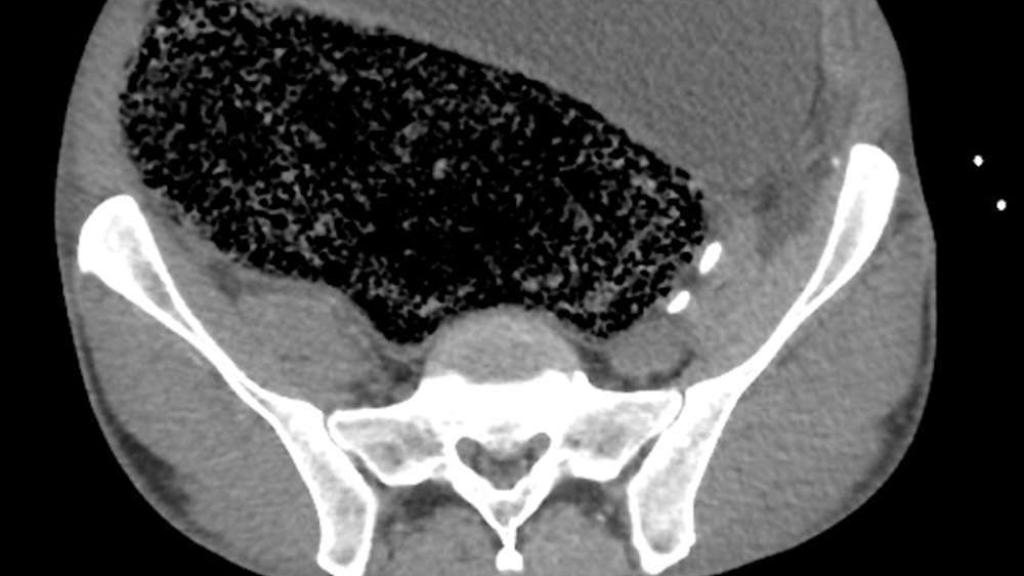

La masa fecal vista en el corte longitudinal, y la presión sobre las arterias. BMJ Case Reports

En este caso, la compactación había llegado al punto de provocar la distensión de su intestino grueso y abdomen, y la enorme masa impactada presionaba contra su arteria ilíaca derecha, provocando la isquemia responsable de cortar el riego a su pierna. También sufría síntomas de fallo renal y acidosis metabólica -una acumulación perniciosa de ácido- que determinaron una intervención quirúrgica inmediata.

"Se procedió a una desimpactación manual de emergencia bajo anestesia general mediante la cual se extrajeron aproximadamente dos litros de heces" - describe el equipo liderado por los doctores Simon Ho, Russel Krawitz y Bill Fleming. Cuatro días después, el paciente pudo abandonar la planta de cuidados intensivos para ser tratado con laxantes. La recuperación completa y el poder caminar sobre sus propio pie no llegó hasta dos semanas después.